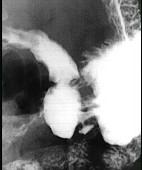

问题 男,24岁,中上腹痛,柏油样便,面色苍白,钡餐检查如图,可能的诊断为 ( )

选项 A、胃间质瘤 B、胃淋巴瘤 C、胃溃疡伴良性狭窄 D、平滑肌肉瘤 E、胃癌

答案 C